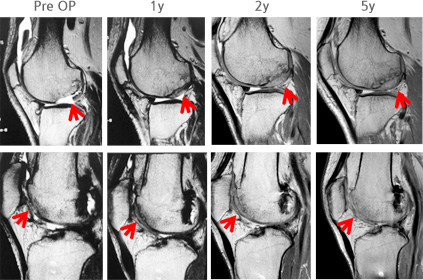

자가 연골 유래 세포치료제인 카티라이프는 연골 결손 및 골관절염 치료제로 쓰인다. 환자의 늑연골 조직에서 세포를 채취해 배양한 뒤 손상된 연골 부위에 이식하는 방식으로 사용된다. 이미 만들어진 연골을 이식해 확실한 연골 재생이 가능하다는 평가를 받는다. 미세천공술 없이도 시술할 수 있지만 세포 채취를 위해 늑골 부위에서 세포를 떼어내는 사전 수술이 필요하다.

이미 국내에서 정식 품목허가를 받은 메디포스트의 카티스템에 더해 소비자의 선택지가 다양화되고 시장이 커지는 셈이다. 카티스템은 2012년 품목허가를 받은 세계 최초 동종 제대혈 유래 줄기세포 치료제다. 연골 손실 부분에 미세천공술을 실시해 줄기세포와 히알루론산나트륨을 투여하면 단백질의 연골 분화가 촉진되고 연골 기질을 분해하는 단백질 활동은 억제되면서 연골 재생을 유도한다.